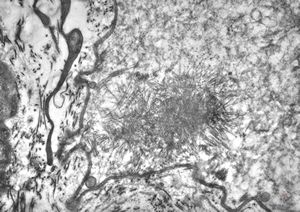

F,56y. | nemaline myopathy v.s.